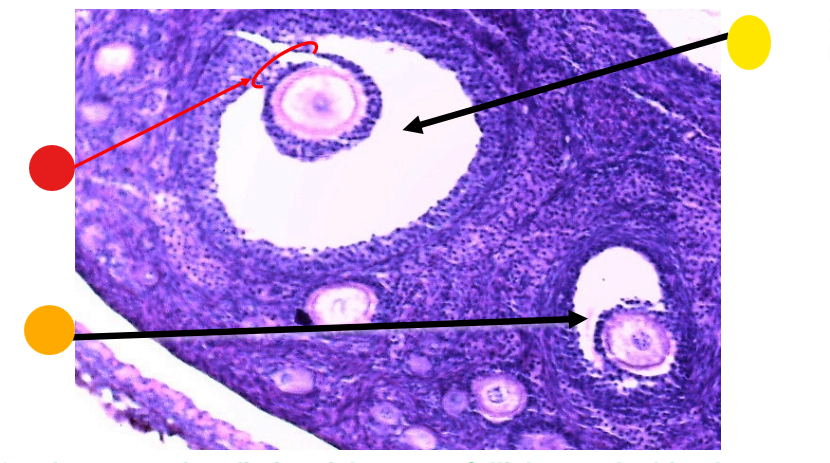

red

primary oocyte

orange

zona pellucida

yellow

granulosa cells

light green

developing thecal cells

What is this

secondary follicle

primordial follicles

red

primary follicles

primordial follicles

red

tunica albuginea

orange

primordial follicles

red

primary follicle

orange

secondary follicles